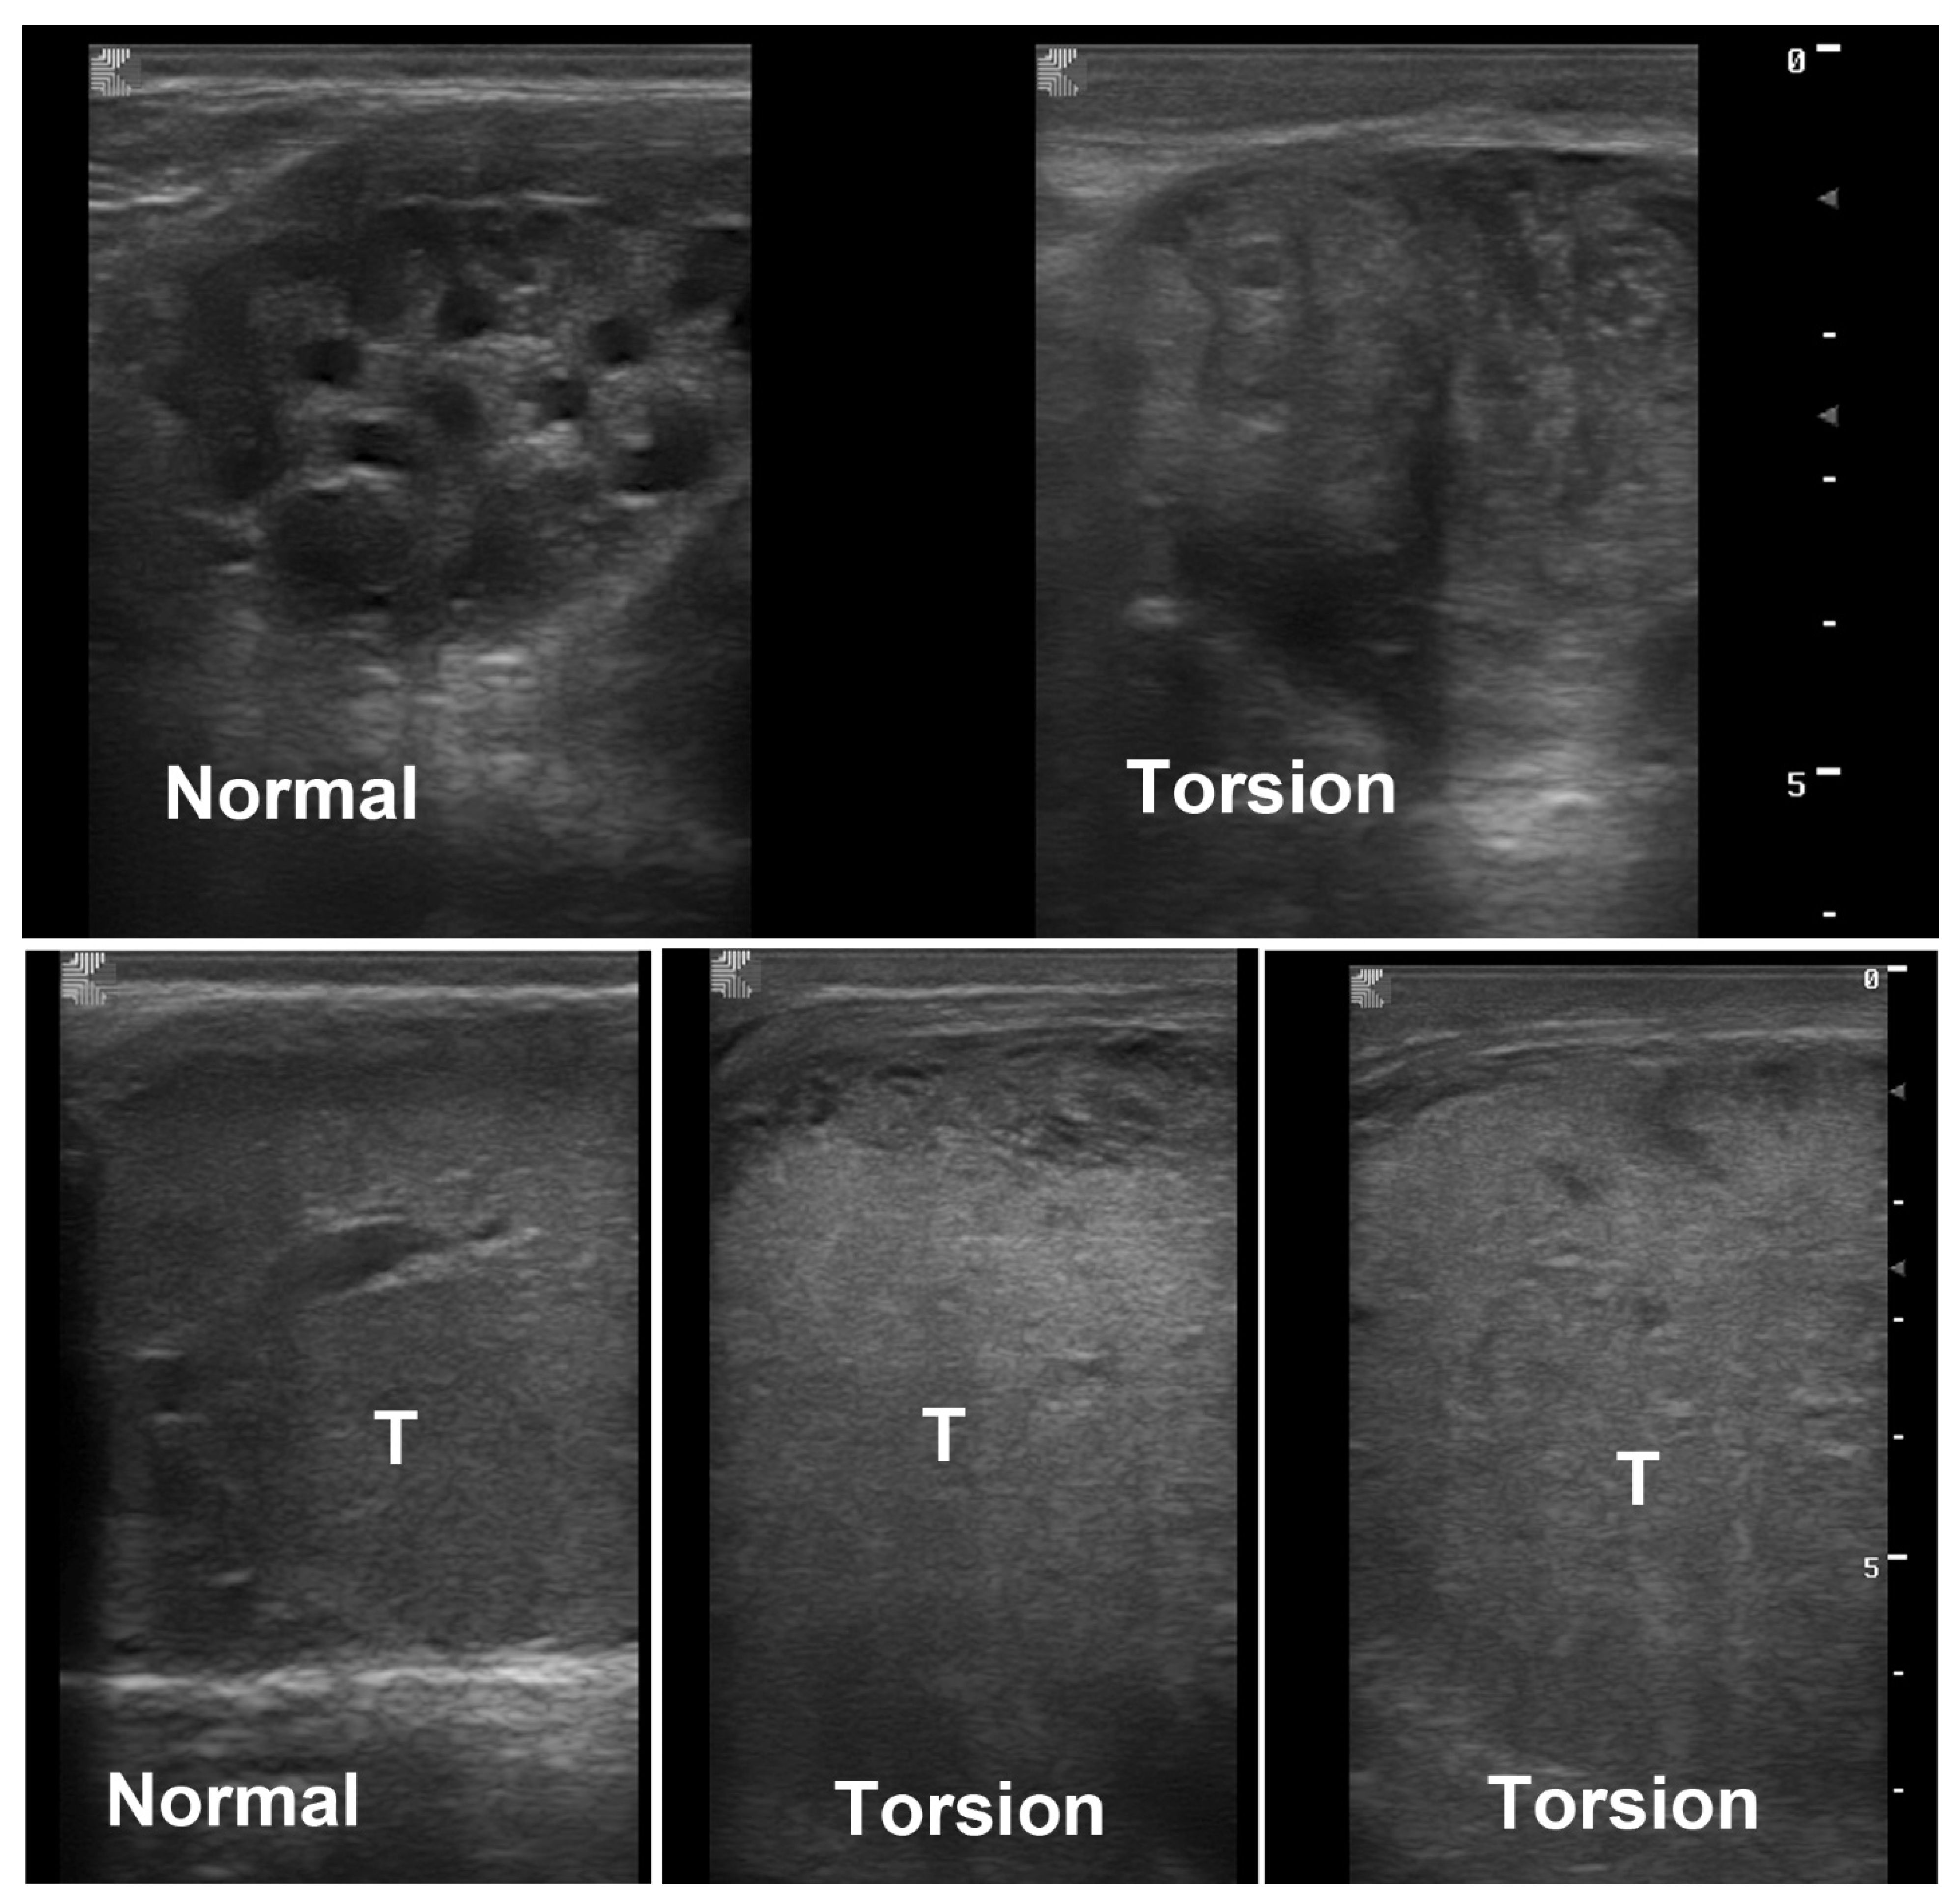

4.3. Torsion of the Spermatic Cord

- Silva, D.F.; Barbosa, D.P.; de Paula Rodrigues, J.; Miranda, T.G.R.; Vilela, V.M.T.; Ignácio, F.S.; Monteiro, G.A. Hemodynamic Evaluation of the Testicular Artery in Stallions with Spermatic Cord Torsion. J. Equine Vet. Sci. 2023, 125, 104617. [Google Scholar] [CrossRef]